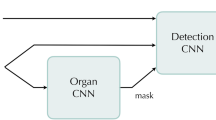

Previous anomaly detection method for PET or PET/CT images [6,7,8] has the limitations detecting anomalies only in a specific organ or region [7, 8] or requiring complicated anatomical standardization [6]. In this paper, we propose a novel anomaly detection CAD method for PET/CT images that can detect anomalies at any location in a simple way. Our method is based on Bayesian deep learning, an intersection between deep learning and Bayesian probability approaches, which can model the uncertainty of tasks as probability distributions [14, 15]. Our CAD models the probability distribution of standard uptake values (SUVs) in a normal training dataset. This allows anomaly detection by calculating Z scores, that is, the difference of the SUV from the mean in units of the standard deviation. Owing to the advantage that images can be processed in raw form in deep learning [16], our method can directly calculate Z scores at once for every pixel from a pair of PET and CT slices.

Our method showed detection performance comparable to those developed in the previous studies of anomaly detection in PET or PET/CT [6,7,8] (Table 2). The main advantage of our method over them is whole-image anomaly detection in a simple way, which is derived from the use of deep learning. Previous studies based on machine learning techniques [7, 8] mainly utilized local features derived from CT values and SUVs. However, it is difficult to learn the variation in FDG uptake between organs only from such local features. To deal with this problem, in those studies, each detector targeted only a specific organ. In this case, abnormal uptake outside the target organs cannot be detected, which loses one of the advantages of anomaly detection, which can detect any type of abnormality. In another study [6], a nonrigid image registration of PET volumes to a standard human body atlas was performed. This anatomical standardization enables whole-body anomaly detection by voxel-wise comparison of the SUVs between images from the target patient and the healthy control group. However, this image registration requires a complicated, multi-step procedure. Such complex preprocessing may reduce the robustness of anomaly detection. Unlike these studies, in our method, both training and anomaly detection can be performed from the PET/CT images in raw form. This naturally provides whole-image anomaly detection, without requiring any complicated preprocessing. This capability to directly process high-dimensional data such as images is a great advantage of deep learning over conventional machine learning methods [16].